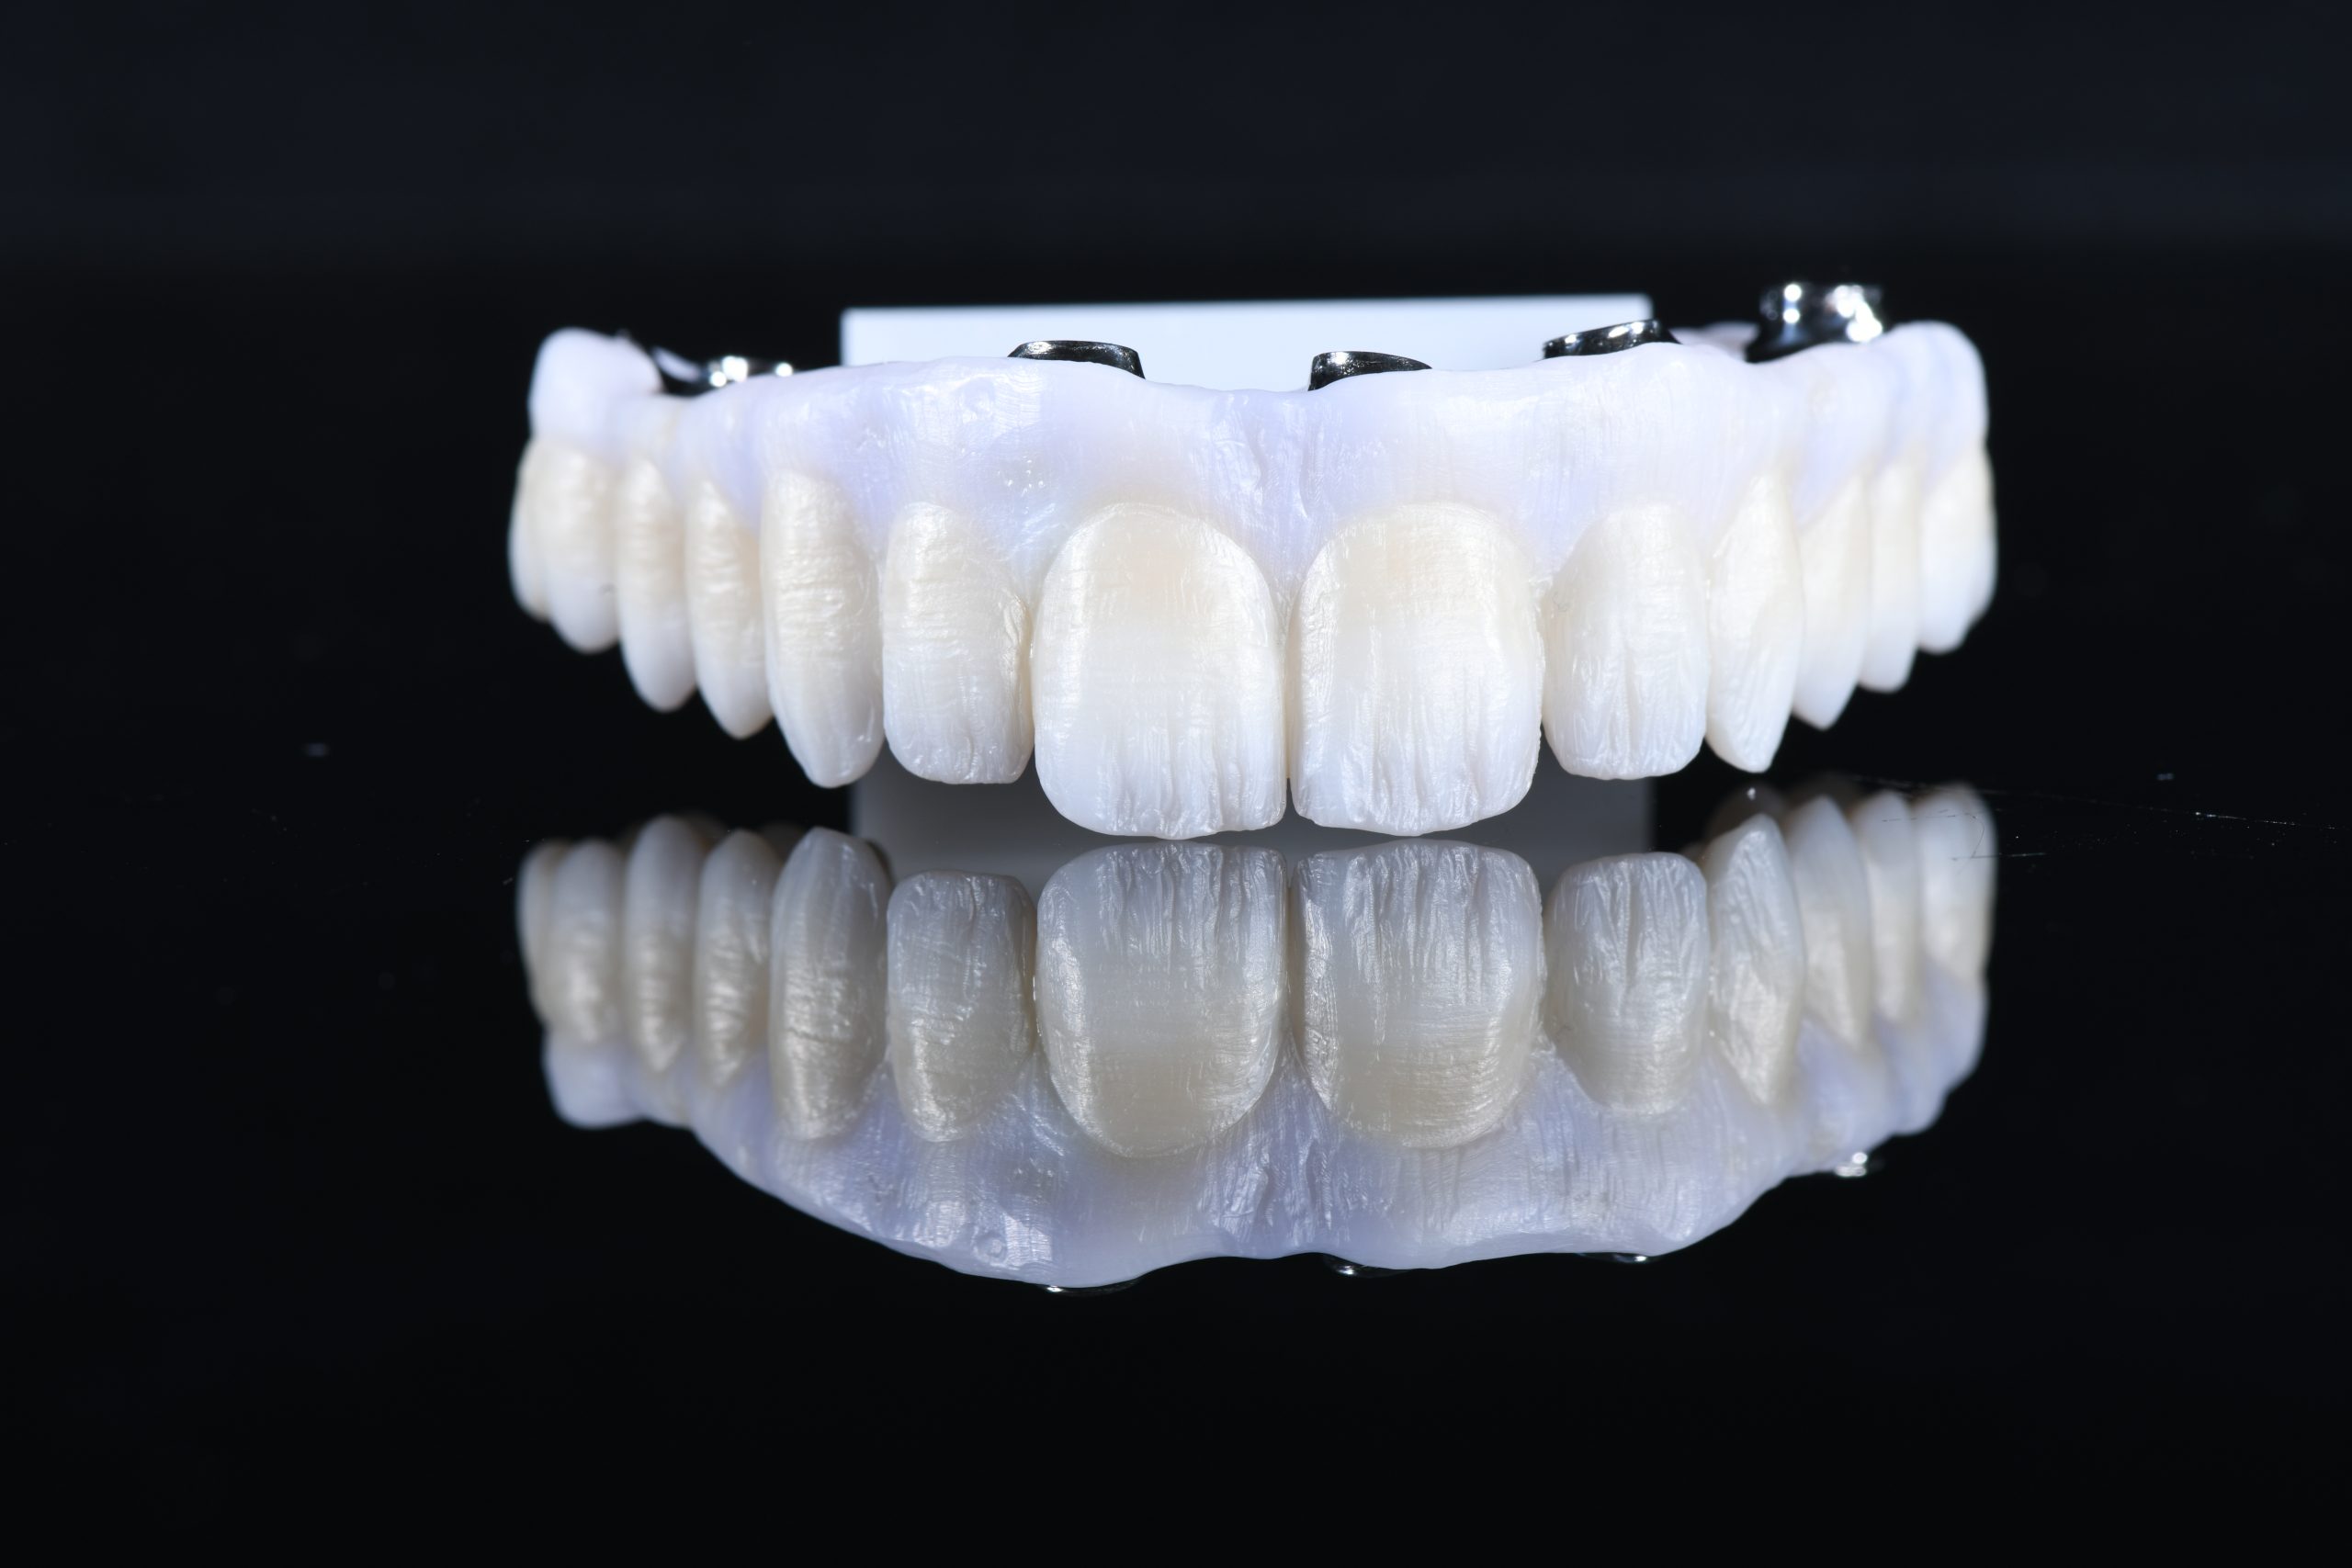

Complete upper rehabilitation directly screwed in zirconia – ceramic

The use of CDP (Complete Digital Patient) as a basis for planning in a case of complete implant rehabilitation with a full arch in zirconia – ceramicised

Total upper and lower rehabilitation in zirconia on implants with titanium reinforcement bars

Complete Digital Patient (CDP): guided surgery for complete upper and lower rehabilitation with zirconia-ceramic screw-retained implants